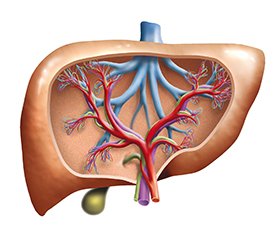

Декомпенсована портальна гіпертензія, ускладнена кровотечею

Незважаючи на те, що ризик смерті від езофагогастральної варикозної кровотечі, спричиненої портальною гіпертензією (ПГ), найвищий у пацієнтів із шлунково-кишковою кровотечею, діагностика й лікування потребують подальшого вдосконалення. Дане дослідження виконано на основі аналізу науково-практичних даних щодо діагностики й лікування хворих на ускладнену ПГ, що дозволяє зрозуміти складність патологічного процесу, причини незадовільних результатів діагностики й лікування, можливості надання планової та екстреної допомоги. Лікування ПГ включає профілактику першої кровотечі, лікування гострої варикозної кровотечі та профілактику повторної кровотечі. Огляд літератури на підставі джерел з бази PubMed, MEDLINE має на меті продемонструвати методи діагностики й лікування кровотечі з вен стравоходу і шлунка в медичних установах з різним рівнем можливостей.

Despite the fact that the risk of death from esophagogastric variceal bleeding caused by portal hypertension is highest in patients with gastrointestinal bleeding, the diagnosis and treatment need to be further improved. This study is based on the analysis of scientific and practical data about the diagnosis and treatment of patients with complicated portal hypertension, which allows us to understand the complexity of the pathological process, the causes of unsatisfactory diagnostic and treatment results, and the possibility of providing routine and emergency care. Management of portal hypertension includes prevention of the first bleeding, treatment of acute variceal bleeding, and prevention of recurrent bleeding. The literature review based on sources from PubMed, MEDLINE aims to demonstrate the methods of diagnosing and treating bleeding from the esophageal and gastric veins in medical institutions with different levels of capacity.